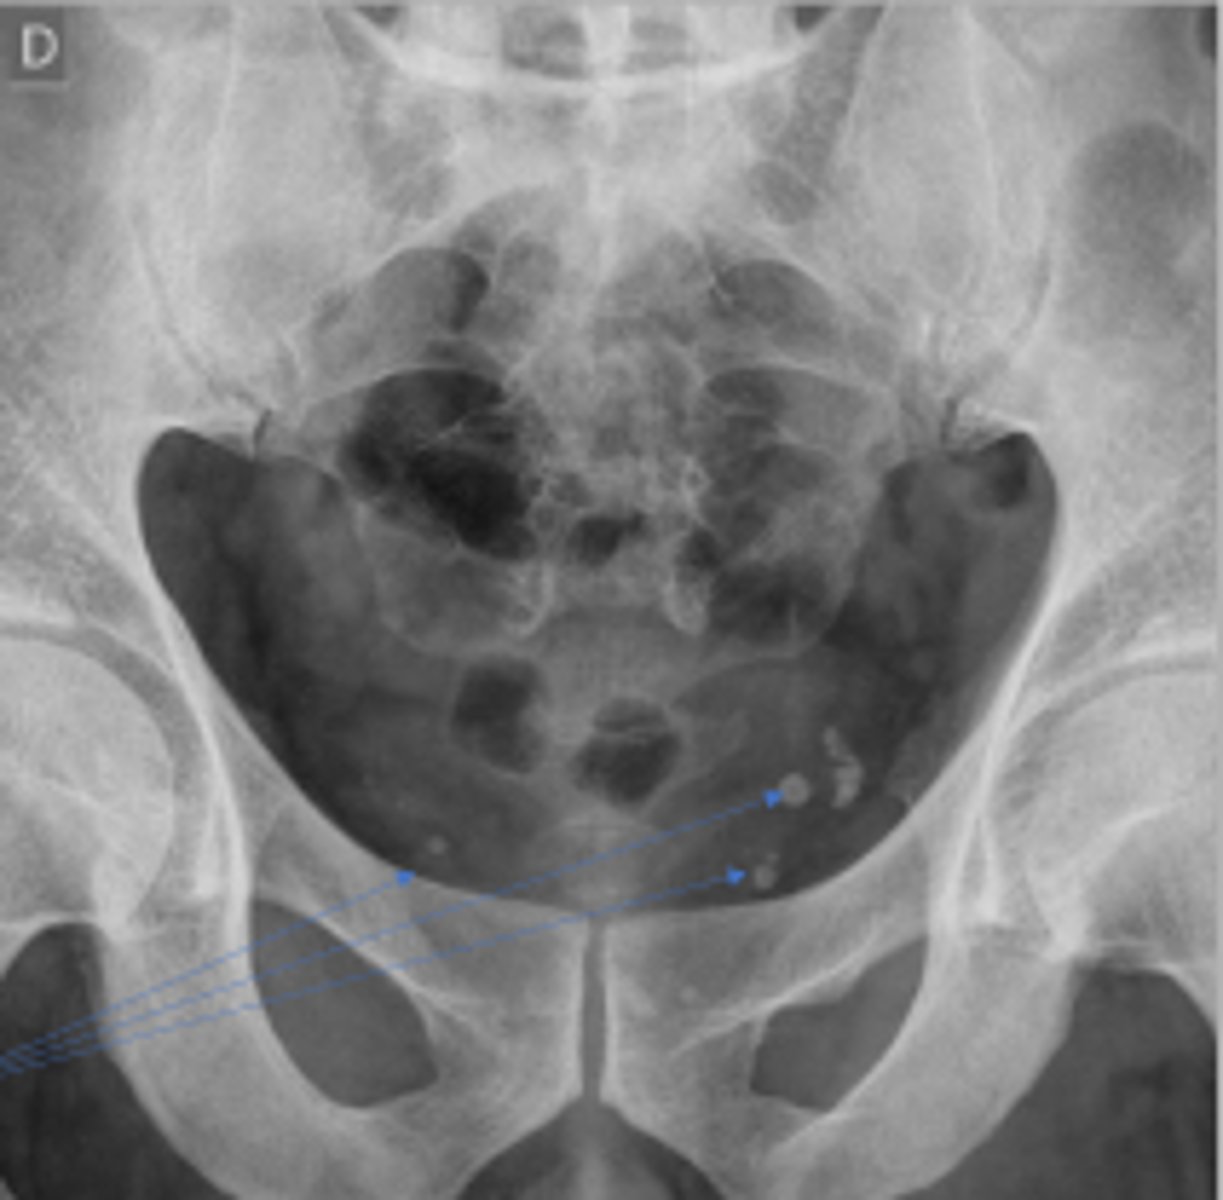

Phleboliths

What are the arrows pointing to?

AP pelvis or bilateral hips

What is the name of the radiographic view?